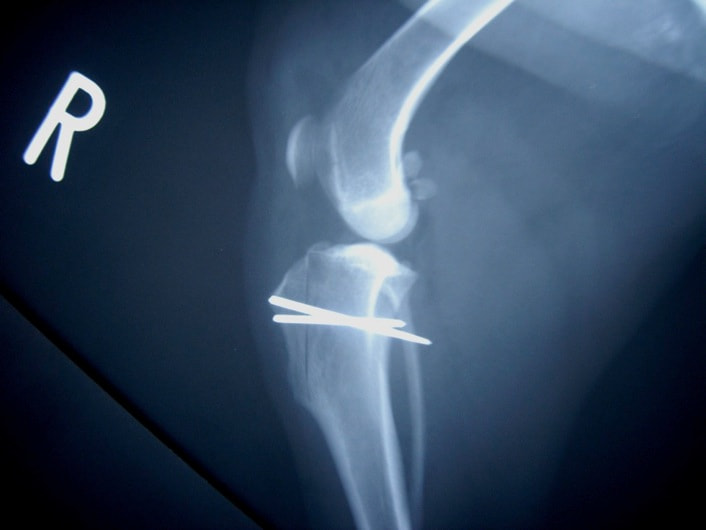

■ 症例24 キャバリア 7か月

左右膝蓋骨内方脱臼(左:グレードⅣ 右:グレードⅢ)

以前から左右後肢の跛行が認められ、整形外科学的検査・レントゲン検査により左右の膝蓋骨脱臼が認められた。症状が重度である左膝の膝蓋骨脱臼整復術を行った。外科手技は縫工筋及び内側広筋の解放、脛骨粗面の外側転位、滑車ブロック形造溝術、内外側関節方の縫縮を実施した。術後一か月時点で、左の膝蓋骨は安定しており経過は良好である。

本症例は成長期における重度の膝蓋骨脱臼であり、術後の再発の可能性もあるため、経過をしっかりと観察していく必要がある。また、今回手術を実施していない右膝に関しても経過を観察し、手術を検討していくこととする。